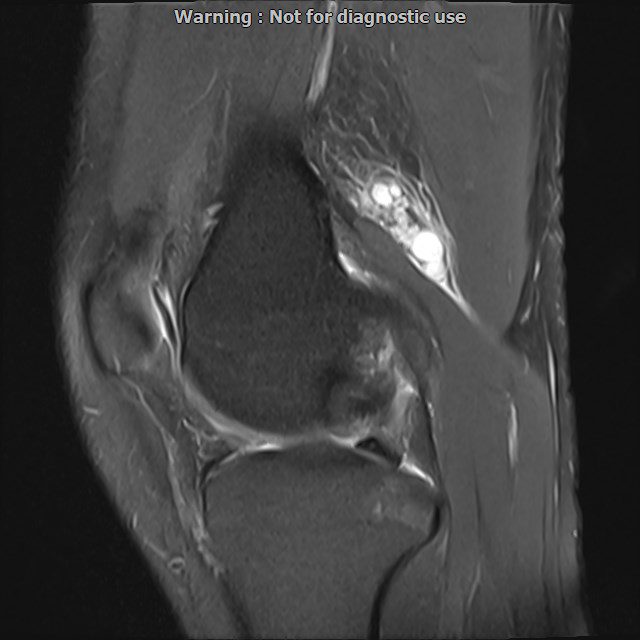

LEFT KNEE MRI

(Without contrast)

Siemens MRI ( magnetom altea 1.5 tesla )

Technique: Sagittal T1, Axial T2 fat sat, coronal & sagittal PD fat sat

– Mild knee joint effusion with soft tissue swelling around the knee

– Low grade partial tearing of ACL with kissing bone bruise in lateral of knee

are seen